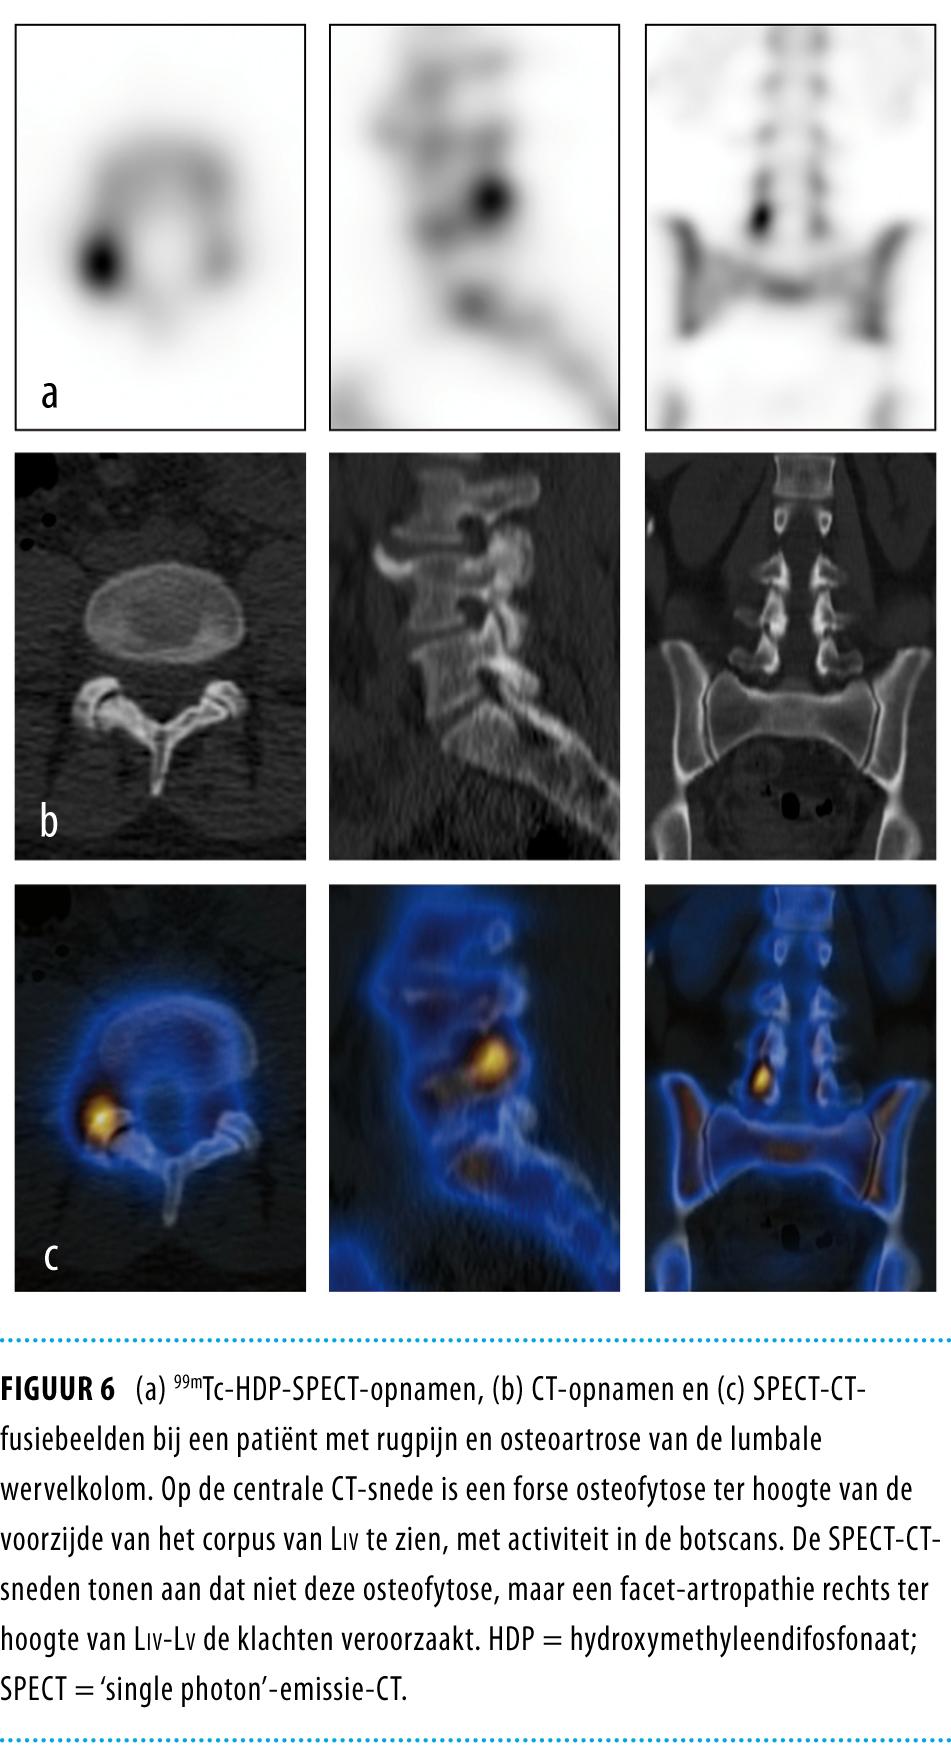

• Er heeft de laatste jaren een snelle ingebruikname plaatsgehad van tomografische en hybride scanners in de nucleaire geneeskunde: ‘single photon’-emissietomografie (SPECT)-CT en positronemissietomografie(PET)-CT.

• SPECT-CT- en PET-CT-technieken leiden tot een hogere diagnostische accuratesse dan de conventionele (niet-tomografisch, niet-hybride) botscintigrafie (botscan).

• Verschillen tussen een botscan met 99mTc-hydroxymethyleendifosfonaat(HDP)-SPECT-CT of met 99mTc-methyleendifosfonaat(MDP)-SPECT-CT en 18F-fluoride-PET-CT-botscan liggen in de beeldkwaliteit, de uitvoering, de kwantificatiemogelijkheden, de stralingsbelasting en de kostprijs.

• Indicaties voor deze technieken lijken vooral te liggen in de in vergelijking met de botscan accuratere detectie van skeletmetastasen en daarnaast, bij patiënten met onverklaarde musculoskeletale pijn, in de diagnostische fase na conventioneel röntgenonderzoek of MRI, en voor de kwantificatie van botmetabolisme.